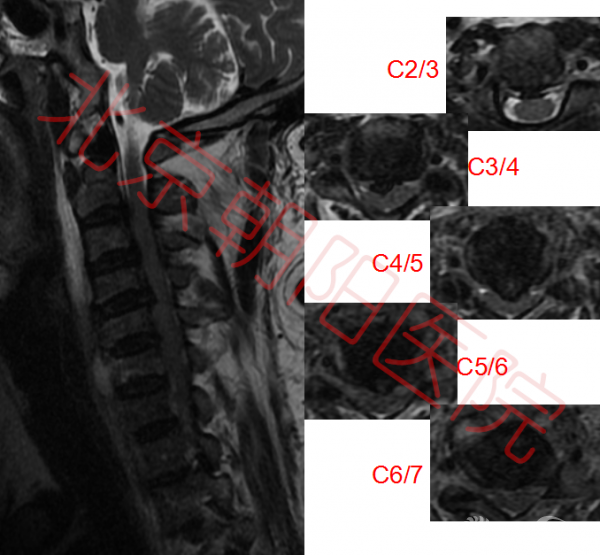

颈椎核磁如图:可见多节段脊髓压迫。

图2:如图可见脊髓多节段受压,C6、C7椎体及椎间盘高信号,C6-C7椎体后方可见高密度影,C5-C8椎体前方高密度影。脊髓内可见高信号区域